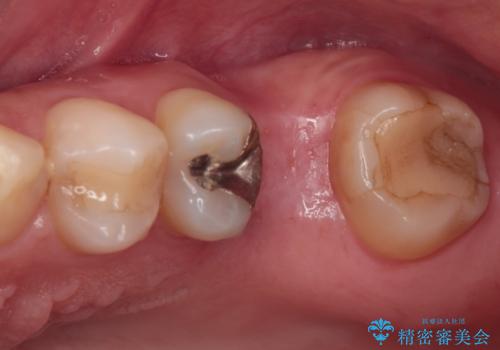

- 近医にて抜歯が必要と診断されたとのことで来院された患者様です。

術前の診査では、歯が破折している可能性が高いものの、確実に抜歯が必要と診断ができない状態でした。

状況次第では抜歯が必要となり、その際にはインプラント治療を行うことを了承いただいた上で、破折していない場合には根管治療を行うこととしました。

土台の材料を外して顕微鏡下で確認したところ、歯根にまで及ぶ破折が認められたため、インプラント治療を行うこととしました。